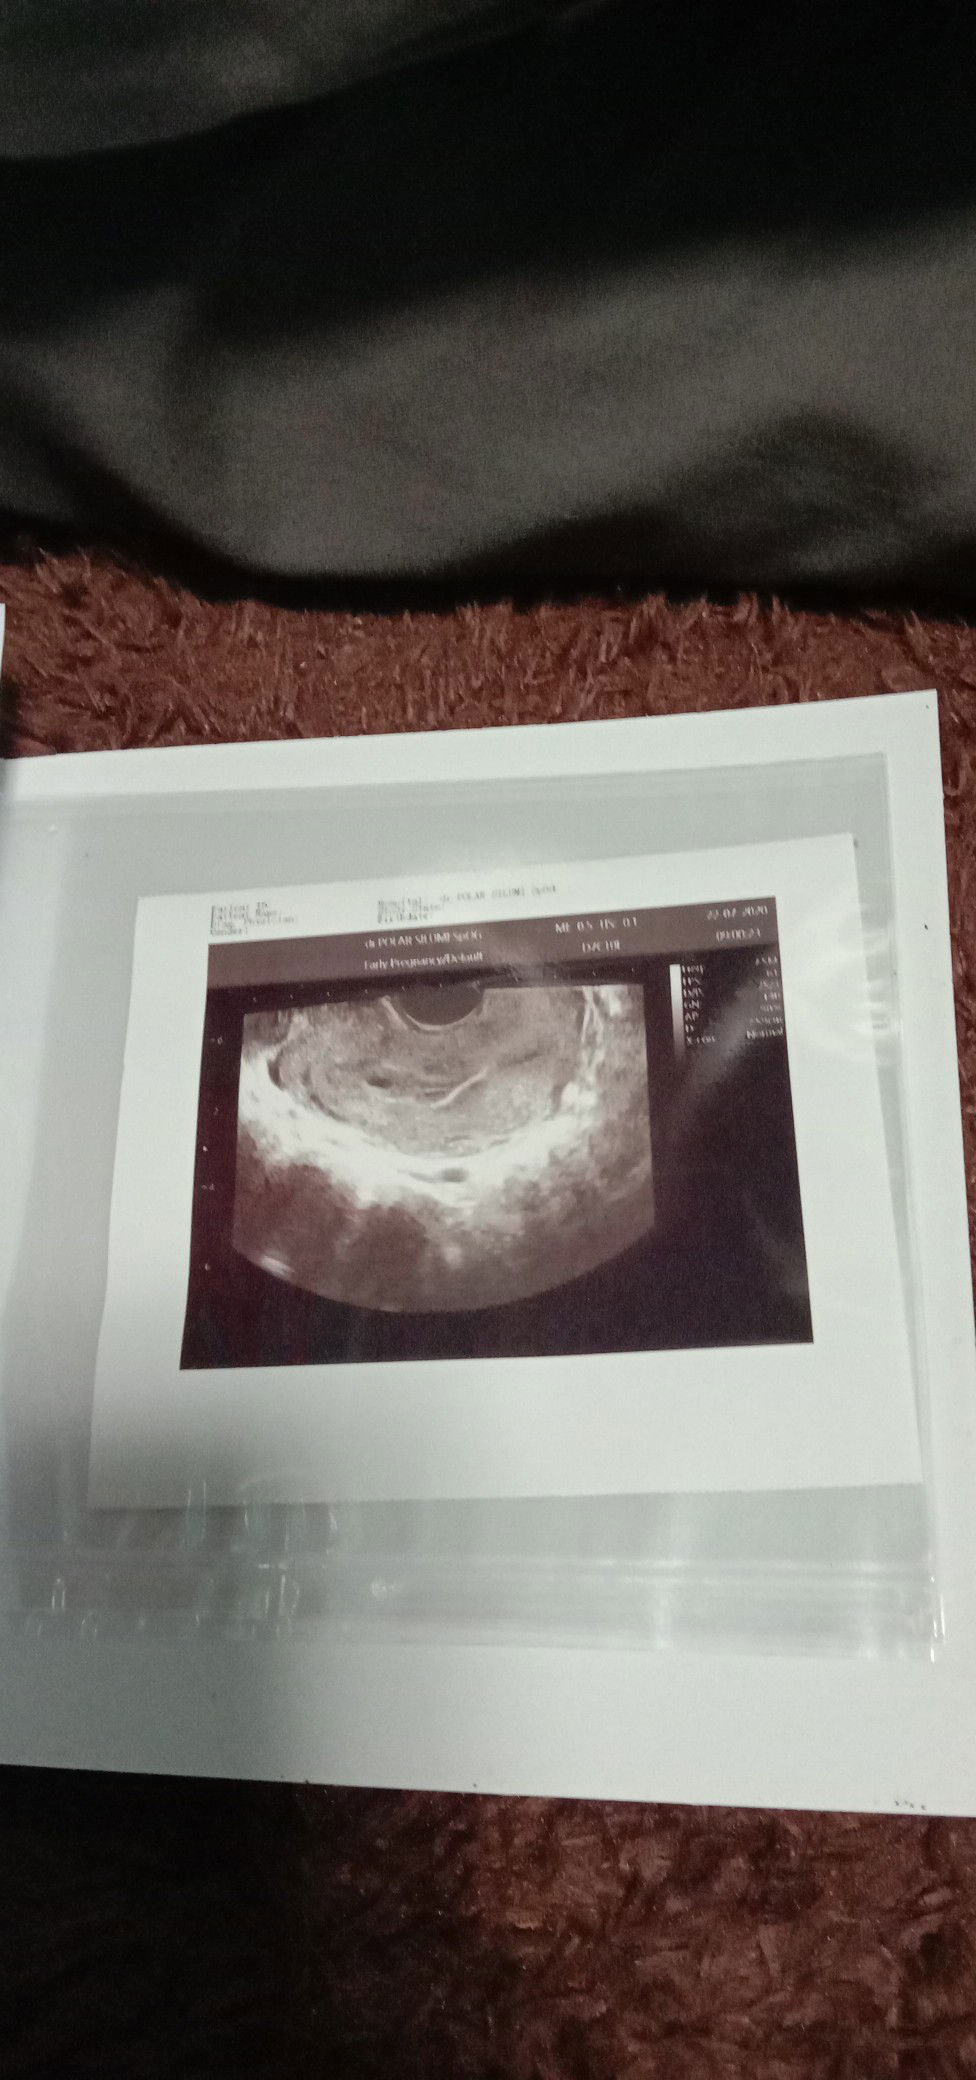

Terimakasih bunda2 disini yg kemaren udah support, dan ngasih saran second opini. Hari ni saya coba second opini dokter lain karena bidan saya juga nyaranin dan dikarenakan darah yg keluar saat BAK semakin byk dan saya merasa sakit di vagina saat BAK dan memang hasilnya Alloh berkehendak lain 🥺 setelah dilakukan Usg lagi ternyata janin nya udah hancur dan trjadi keguguran😭semoga saya bisa ikhlas, kuat, dan sehat dan saya yakin Alloh kasih kepercayaan lagi buat saya suatu hari nanti.. Amiin

Usia kehamilanku baru 6minggu, tetapi baru2 ini trjdi flek yg keluar saat buang air kecil dan sering ngerasain sakit perut bagian bawah, hasil usg menyatakan ada bulatan kecil yg kata dokter takutnya hamil dluar kandungan dan mnta di evaluasi 2minggu kemudian, untuk flek karena ada riwayat saat ank pertama tp untuk hamil dluar kandungan aku baru dgr, bahaya ga sih itu bun???